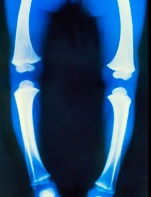

enough, it can lead to things like

rickets (in children) and osteomalacia -

ie muscle pain and weakness, and loss of

bone strength (in adults and the elderly).